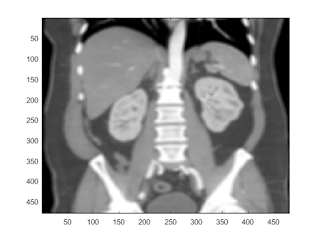

unsharp mask

b = fspecial('unsharp'); subplot(221); imagesc(b); colorbar; subplot(222); imagesc(I); subplot(224); I2 = conv2(I,b,'same'); imagesc(I2);